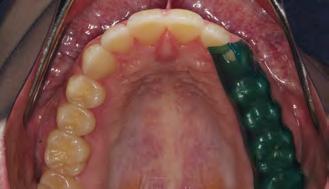

08 — Preparaciones terminadas de los dientes anteriores en el maxilar superior e inferior (preparación parcial). 08b

Si es posible, para la cementación adhesiva se coloca un dique de goma para aislamiento absoluto. Alternativamente, antes de la cementación se coloca un hilo de retracción de grosor 00 en el surco, para tener buen acceso a los márgenes de la preparación (Fig. 12). Los dientes adyacentes se aíslan con cinta de teflón. Normalmente colocamos las coronas en pares. Después de grabar con ácido fosfórico al 37 %, el muñón del diente muestra que casi toda la preparación entera está en la zona del esmalte. La dentina es visible solo en áreas aisladas, expuesta por la actividad parafuncional de la paciente.